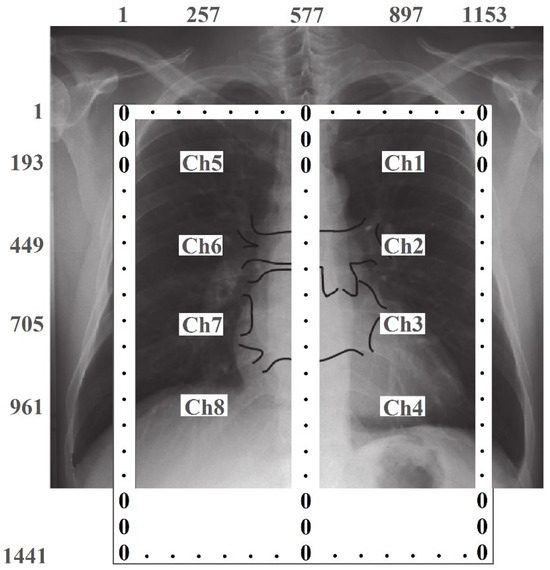

The algorithm for converting spatially distributed pulmonograms into two-dimensional dynamically changing color images is performed in several stages. The size of the matrix for visualization was chosen as 1441 × 1153 pixels, which should approximately correspond to the proportions of the human chest. Since the measurements were carried out only at 8 points of the matrix, the missing elements between the 8 measurement results and the data from the a priori geometric model (boundary conditions) of the lungs were interpolated. Figure 11 schematically shows the lungs, the location of the emitter matrix, and their numbering, as well as the size of the image matrix with pixel numbering. Since, according to the a priori lung model, changes in the level of the signal associated with breathing should not occur outside and between the lungs, the edge elements of the image matrix and the elements of column 577 are assigned zero values.

Figure 11. Setting the boundary values of the image matrix. The size of the display area is 1441 × 1153 pixels. The background image was taken from [20]. The spatial measurement points correspond to the following elements in the image matrix: Ch1 (193, 897); Ch2 (449, 897); Ch3 (705, 897); Ch4 (961, 897); Ch5 (193, 257); Ch6 (449, 257); Ch7 (705, 257), and Ch8 (961, 257).